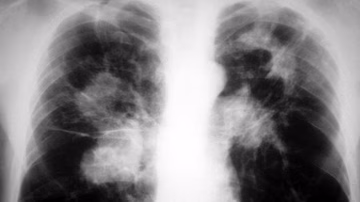

Svjetski dan borbe protiv tuberkuloze: Prošle godine u Federaciji BiH oboljele 232 osobe, umrlo osam Vijesti | 24. mar. | 0